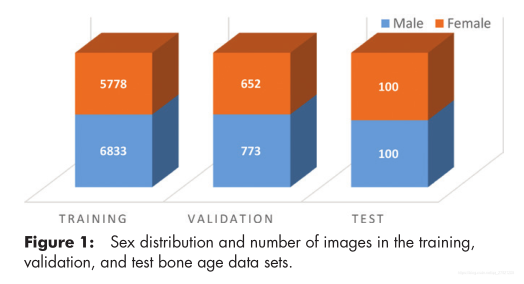

提供了由14236张手部X射线照片组成的数据集(12611个训练集,年龄1-228个月整数,非连续分布,1425个验证集,200个测试集),几乎所有方法都使用基于一个或多个卷积神经网络(CNN)的深度神经网络技术。基于MAD的最佳五个结果分别为4.2、4.4、4.4、4.5和4.5个月。